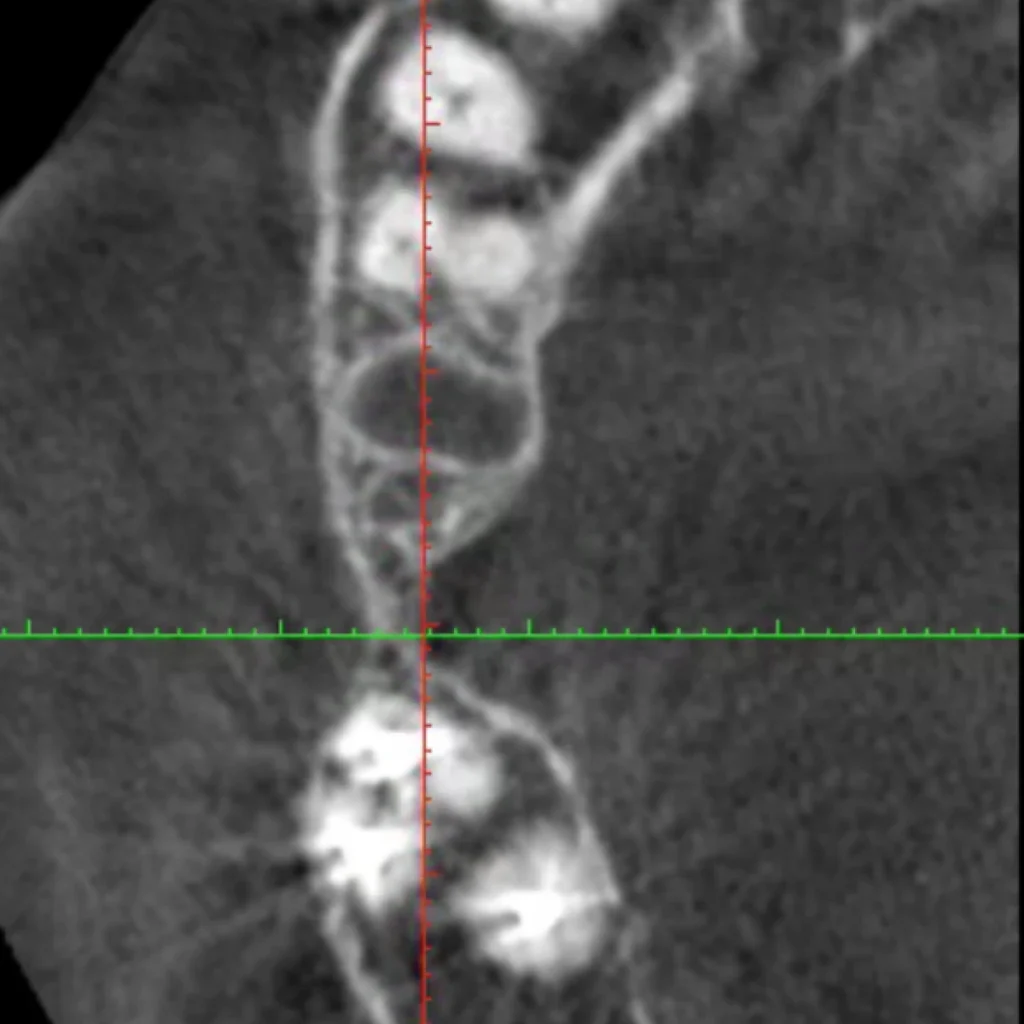

Un cone beam (équivalent d’un scanner) est réalisé sur place afin de valider le diagnostique et de vous proposer le traitement adapté à votre situation. Certaines font intervenir des biomatériaux (os de banque d’origine humaine ou animale; os de synthèse; os autogène prélevé directement dans votre bouche lors de l’intervention).

- Le scanner réalisé au cabinet met en évidence un défaut osseux majeur nécessitant une greffe osseuse complexe pour réhabiliter la zone par 2 implants.

- Après 4 à 6 mois de cicatrisation, un scanner est à nouveau effectué pour s’assurer du bon volume osseux pour mettre en place nos implants.